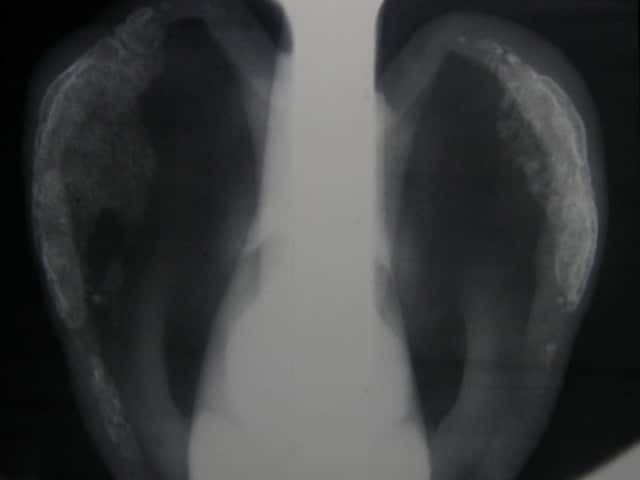

Xray of auricular relapsing polychondritis

Relapsing polychondritis